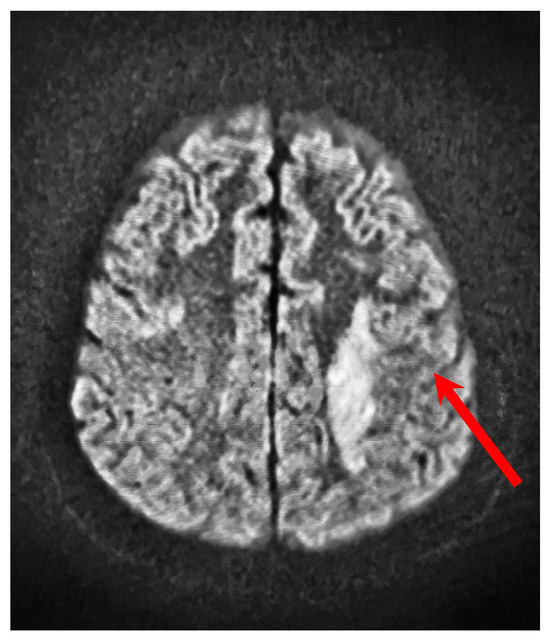

3. Case Presentation